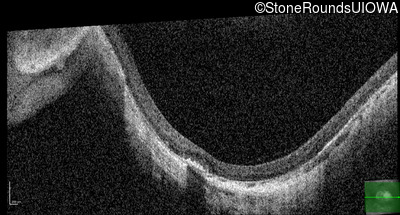

Optical Coherence Tomography - Right - 10/300

Exemplar / OCT Stack

OCT Stack